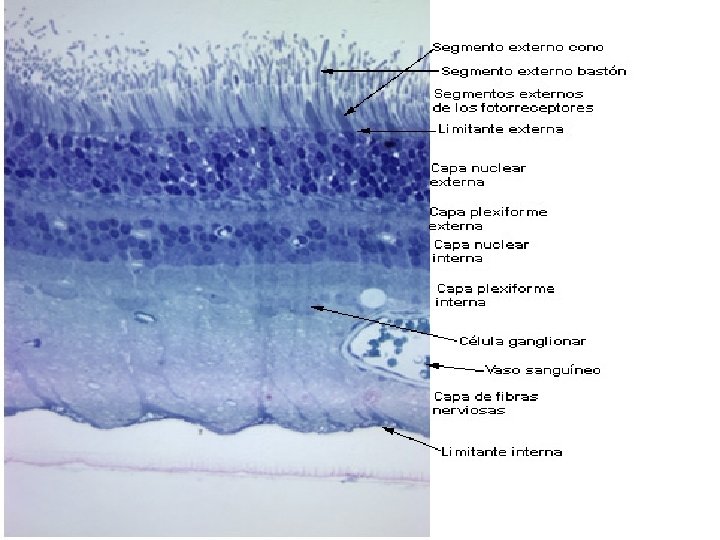

RETINA

CAMADA INTERNA NERVOSA- FOTOSSENSITIVA A retina fica na parte interna do globo ocular e é formada por duas porções: posterior sensitiva e anterior não-sensitiva ou cega. A parede mais externa da retina originará uma fina camada de epitélio cúbico simples, composta de células pigmentares (epitélio pigmentar da retina). A outra parte da retina (mais interna) é constituída de fotorreceptores. Essas camadas não estão fortemente unidas uma à outra, enquanto que a camada pigmentar está muito aderida à coróide. Esse epitélio pigmentar é composto por células cúbicas com núcleo na posição basal. E, a parte fotossensitiva da retina compõe-se das seguintes camadas: Membrana limitante externa Células fotossensitiva – cones e bastonetes; Neurônios bipolares – unem os cones e os bastonetes às células ganglionares; Células ganglionares – contato com os neurônios bipolares na parte externa e, na interna, com fibras nervosas que vão originar o Nervo Óptico.